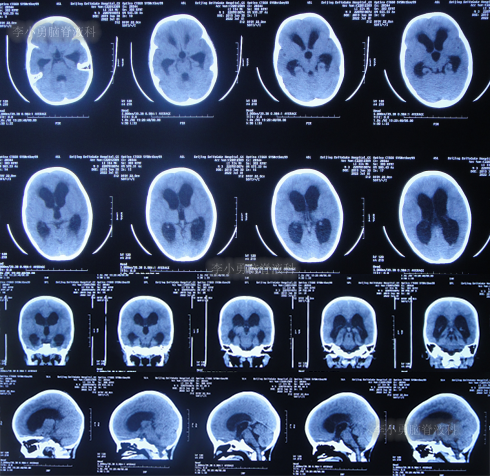

入院当天查头颅CT示脑室扩张(图-8)。

图-8:2022年7月1日入院时头颅CT